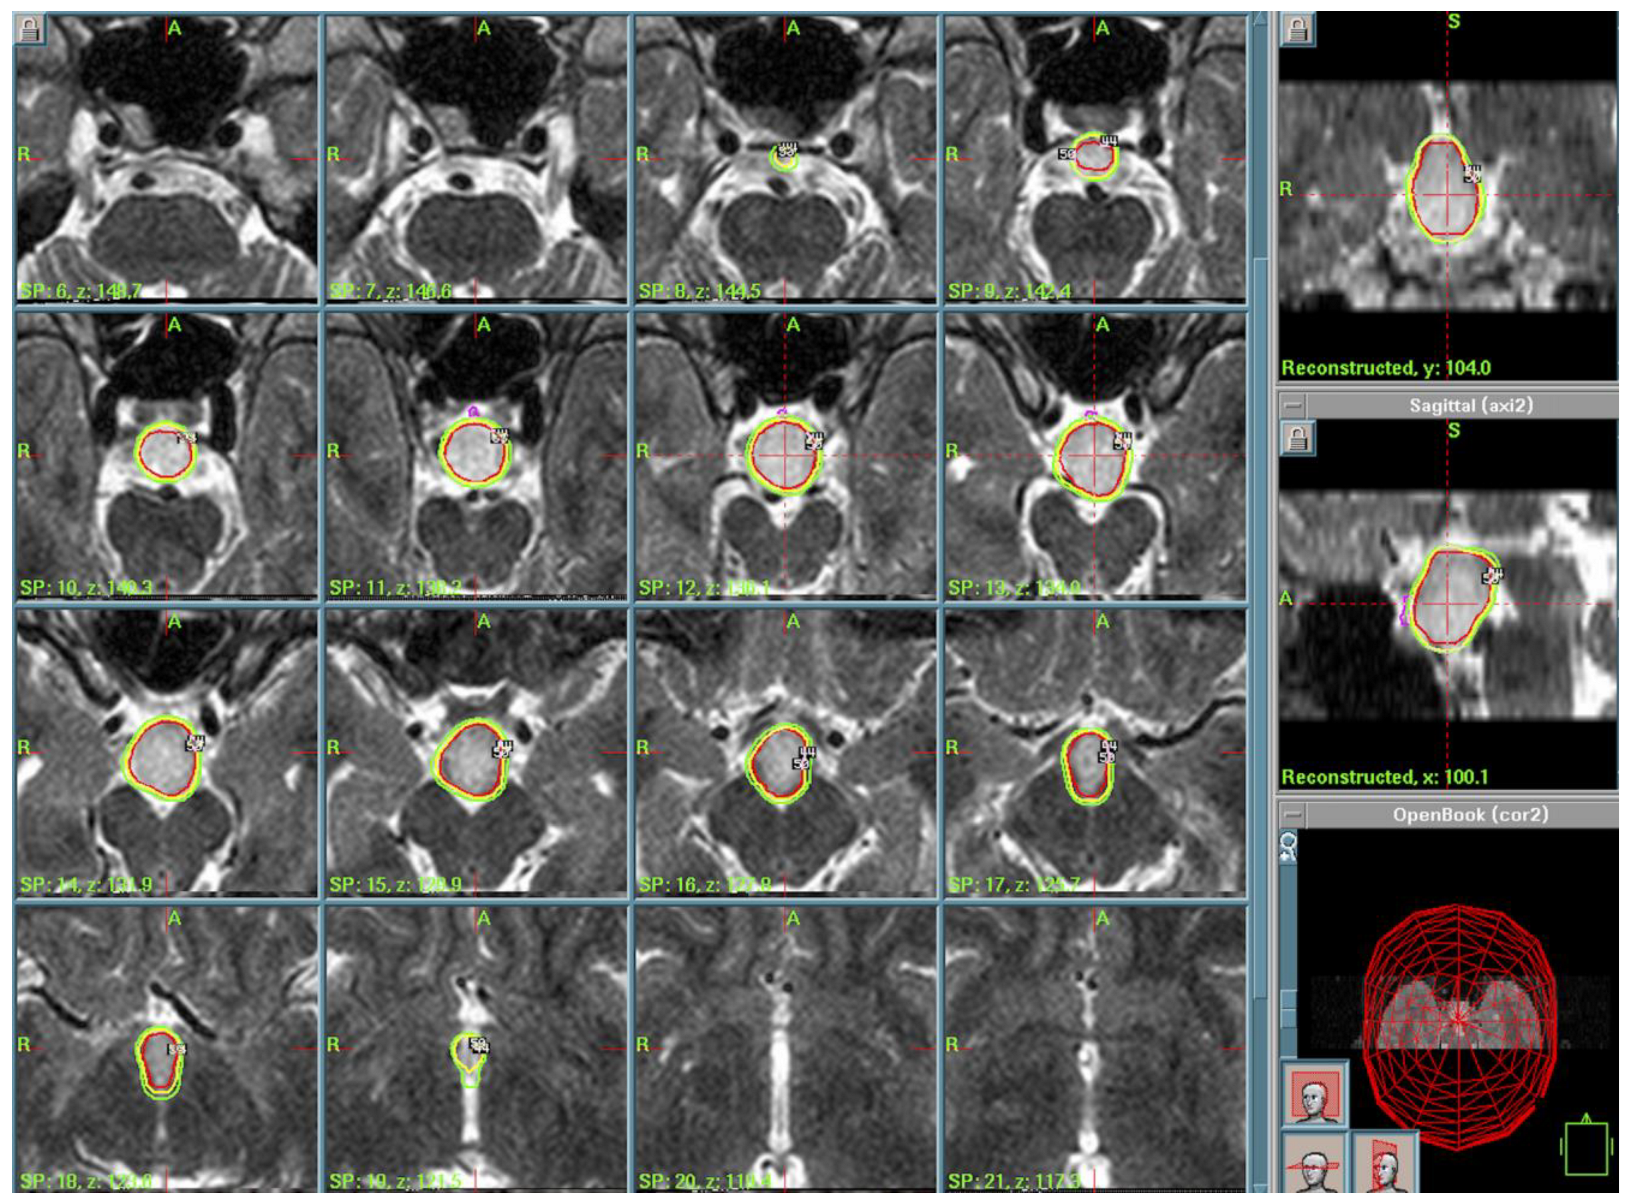

3.6. Choroid Plexus Papilloma (CPP)

| 9. | Ectopic Choroid Plexus Papilloma (CPP) | Dose Staging: PI of 50%, PD of 10 Gy, MD of 20 Gy, PI of 50%; PD of 9 Gy, MD of 18 Gy after 1 month | 2011–2019 |